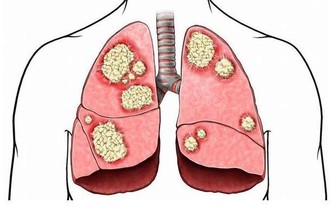

而喝酒臉紅正是因為體內缺乏將乙醛轉化為乙酸的酶,

導致乙醛在體內蓄積,損害肝臟功能,增加肝病風險,長期飲酒也會導致食道癌的發生。

美國《PlosMedicine》雜誌刊載了一篇名為《酒精性臉紅的反應:來自於飲酒關於食管癌未知的風險因素》的論文,美國國家酗酒與酒精中毒研究所和日本久里濱酒精過敏研究中心的研究人員的聯合研究發現,對於體內缺乏乙醛脫氫酶2或這種酶不能正常發揮作用的人群來說,患食道癌的風險隨酒精攝入量的增多而增大。